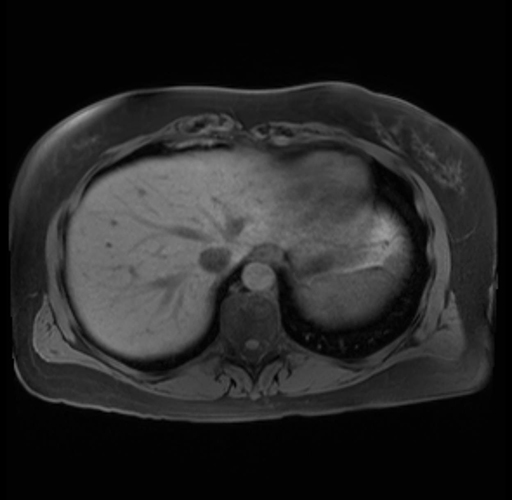

Imaging Analysis

Look through the patient's CT scan to identify any areas of concern for the necessary procedure.

Based on your CT findings, which issue(s) are present and would give reason for "planned slowing down moment(s)" in this case?